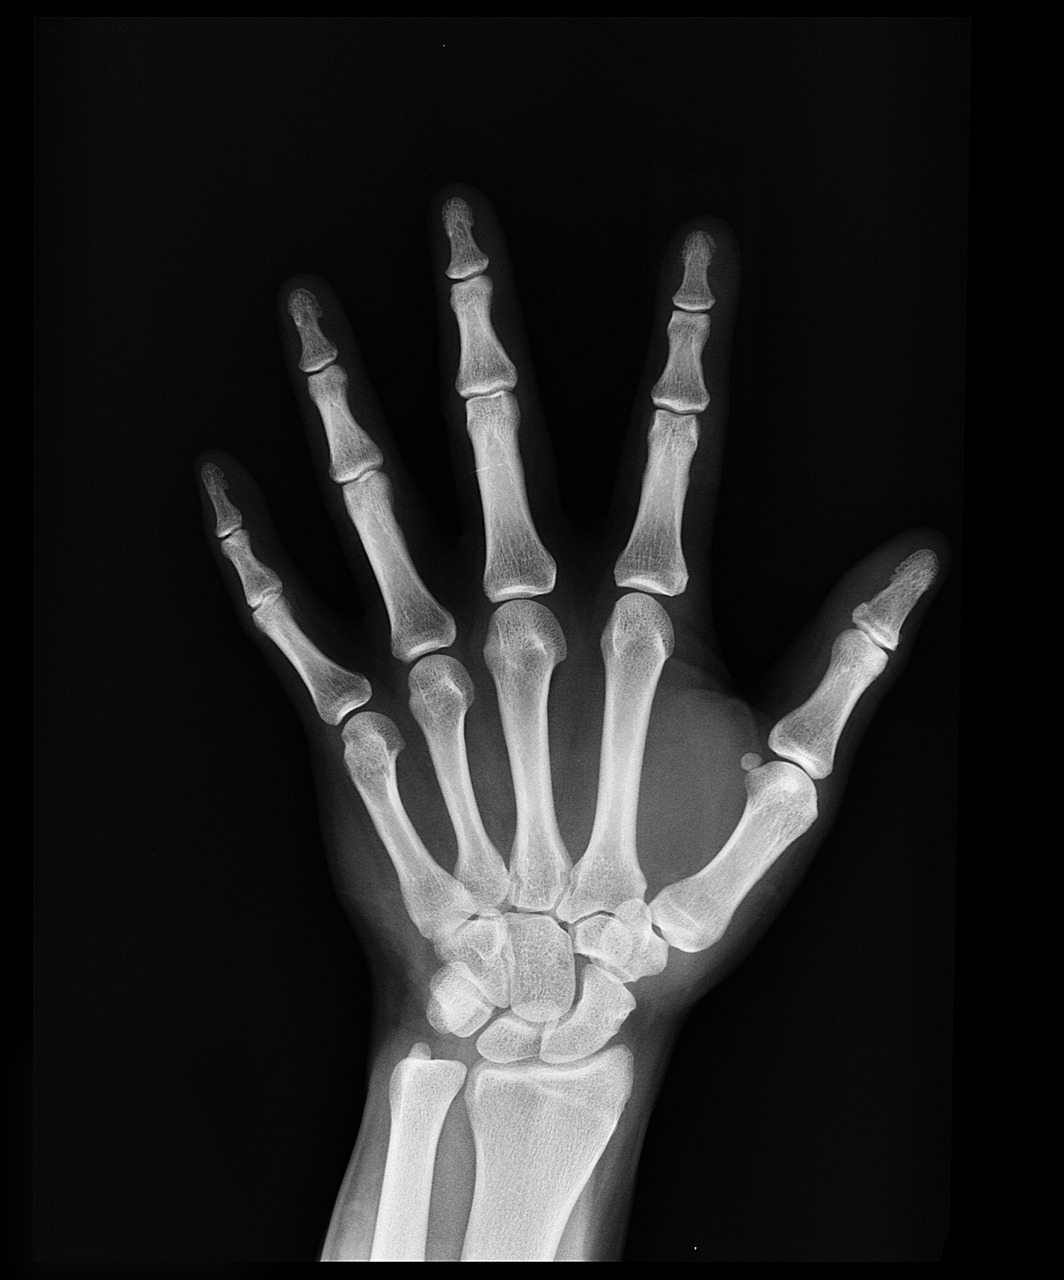

そして、レントゲンを見ると緊急手術で粉々だった骨は見事に元の位置へ戻っていたのです。

(イメージ画像です)

医師の技術に驚き、そんなに悪くはないのでは・・・期待せずにいられませんでした。

しかし、医師の見解は、厳しいものでした。

血管がボロボロで、指先にある毛細血管の修復が難しいこと、血が通わないとどんどん壊死してしまうこと、機械のバイ菌が悪影響を与えること・・・悪い情報ばかりでした。